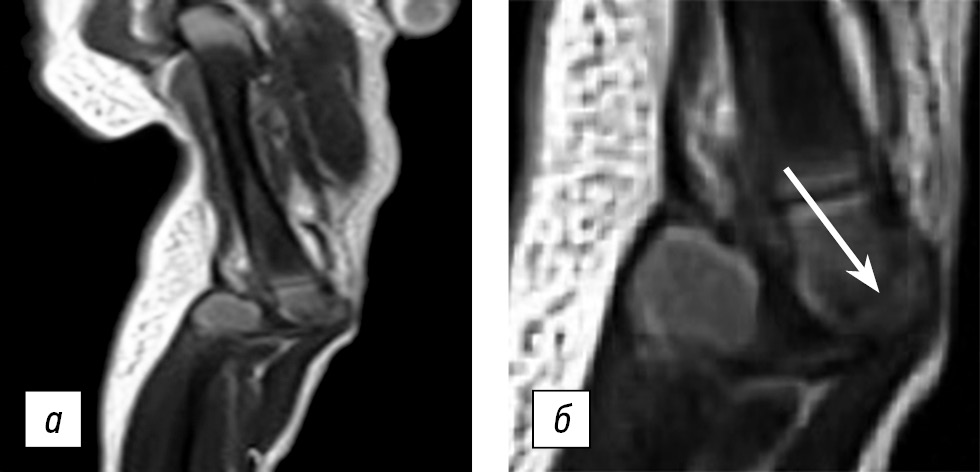

Therefore, attempts of correction were stopped until complete epithelialization of the injury sites with fixation preservation. The child was transferred to the surgical department for further follow-up and treatment. On day 6, conservative treatment was continued using the above-mentioned method. On day 10, an increased passive flexion by 15° in each knee joint was obtained (in comparison with the results of correction on day 1 of life). The clinical examination revealed femoral condyles in the popliteal region, with edema of the right knee joint. Magnetic resonance imaging of the knee joints was performed. These studies confirmed the preservation of complete knee dislocation on both sides. Patellar aplasia and an impression fracture of the epiphysis of the right femur were also identified (Fig. 2).

Fig. 2. Patient P., age 10 days, during treatment: a — preservation of knee dislocation, patella aplasia, impression fracture of the epiphysis of the right femur; b — the fracture line is shown